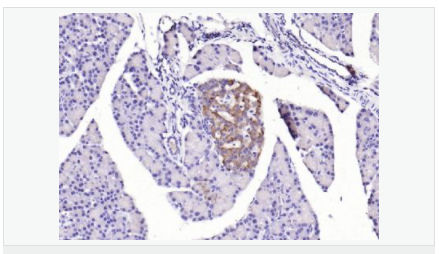

| 產品應用 | WB=1:500-2000 ELISA=1:5000-10000 IHC-P=1:100-500 IHC-F=1:100-500 IF=1:100-500 (石蠟切片需做抗原修復) not yet tested in other applications. optimal dilutions/concentrations should be determined by the end user. |

| 產品介紹 | The protein encoded by this gene is a leucine-rich repeat-containing receptor (LGR) and member of the G protein-coupled, 7-transmembrane receptor (GPCR) superfamily. The encoded protein is a receptor for R-spondins and is involved in the canonical Wnt signaling pathway. This protein plays a role in the formation and maintenance of adult intestinal stem cells during postembryonic development. Several transcript variants encoding different isoforms have been found for this gene. [provided by RefSeq, Sep 2015] Function: Receptor for R-spondins that potentiates the canonical Wnt signaling pathway and acts as a stem cell marker of the intestinal epithelium and the hair follicle. Upon binding to R-spondins (RSPO1, RSPO2, RSPO3 or RSPO4), associates with phosphorylated LRP6 and frizzled receptors that are activated by extracellular Wnt receptors, triggering the canonical Wnt signaling pathway to increase expression of target genes. In contrast to classical G-protein coupled receptors, does not activate heterotrimeric G-proteins to transduce the signal. Involved in the development and/or maintenance of the adult intestinal stem cells during postembryonic development. Subunit: Identified in a complex composed of RNF43, LGR5 and RSPO1. Subcellular Location: Cell membrane; Multi-pass membrane protein Tissue Specificity: Expressed in skeletal muscle, placenta, spinal cord, and various region of brain. Expressed at the base of crypts in colonic and small mucosa stem cells. In premalignant cancer expression is not restricted to the cript base. Overexpressed in cancers of the ovary, colon and liver. Similarity: Belongs to the G-protein coupled receptor 1 family. Contains 16 LRR (leucine-rich) repeats. Contains 1 LRRNT domain. SWISS: O75473 Gene ID: 8549 Database links: Entrez Gene: 8549 Human Entrez Gene: 14160 Mouse Omim: 606667 Human SwissProt: O75473 Human SwissProt: Q9Z1P4 Mouse Unigene: 658889 Human Unigene: 42103 Mouse Unigene: 214063 Rat Important Note: This product as supplied is intended for research use only, not for use in human, therapeutic or diagnostic applications. Lgr5基因(Wnt細胞信號系統(tǒng))是一種G蛋白偶聯受體,已經被確定為幾種成年組織和癌癥中干細胞的一個獨特標記。Lgr5最初是在結腸癌細胞中發(fā)現的,有報道稱:在惡化前的小鼠腺瘤中也有發(fā)現,這說明Lgr5很可能也是其他組織成體干細胞和癌癥干細胞的標志物。 |